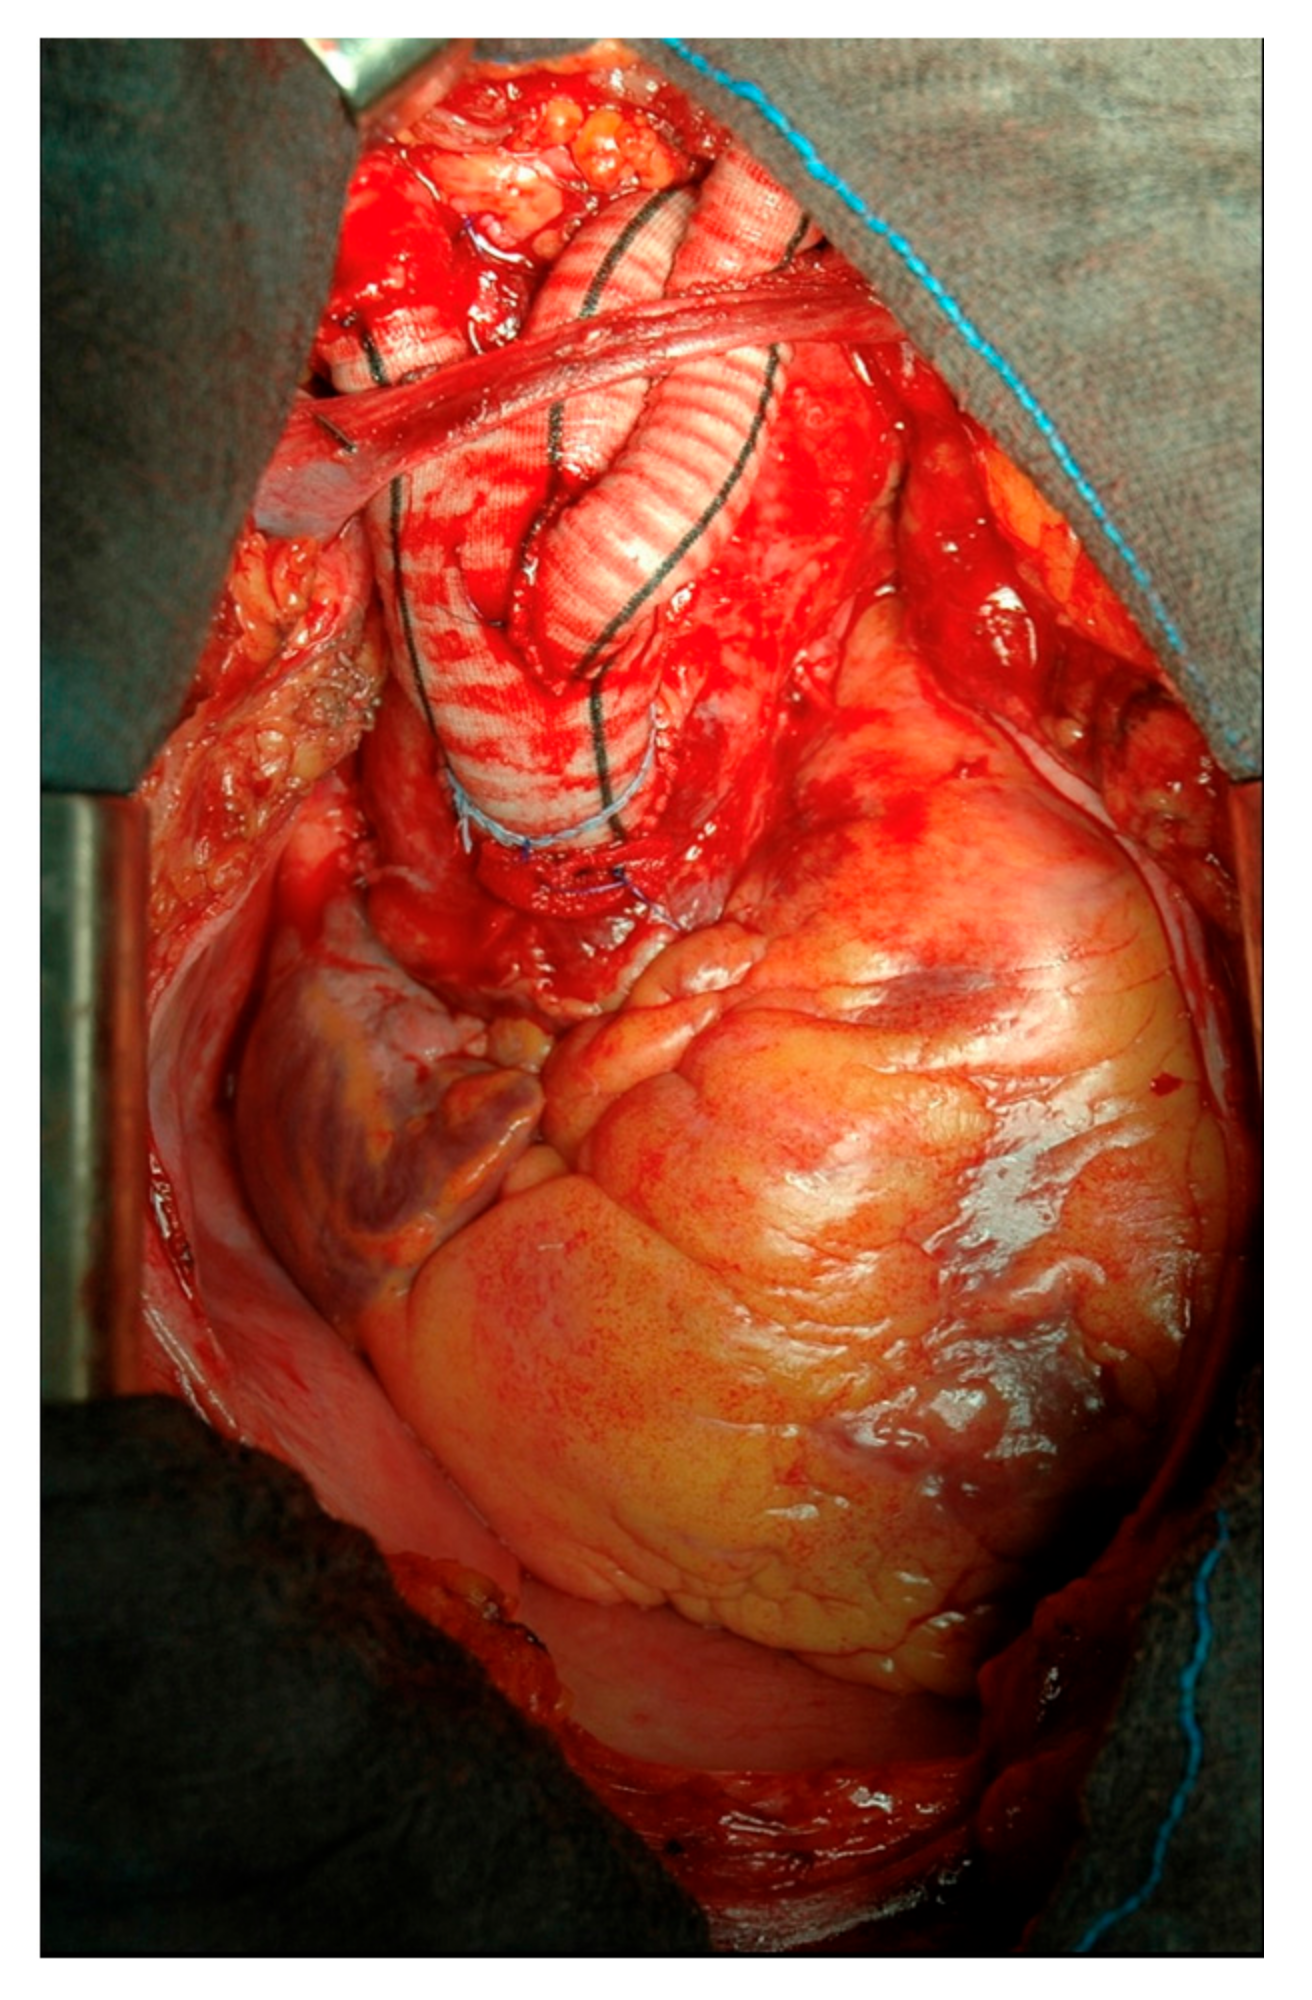

For type I arch debranching, heparinization is started to reach a coagulation activated time longer than 250 s. After reaching a mean blood pressure of 80 mmHg by pharmacological therapy or by ventricular pacing, the ascending aorta is tangentially clamped with a side-biting clamp and the proximal part of a bi- or trifurcated Dacron vascular prosthesis (Uni-Graft K-DV; Aesculap, Tuttlingen, Germany) is sutured end-to-side to the aorta. Preoperative CT scan, transesophageal echocardiography and digital inspection are the tools to determine the position on the ascending aorta for proximal anastomosis, in order to avoid atherosclerotic plaques and to obtain an adequate landing zone for the TEVAR. Once the proximal anastomosis is completed, the first limb of the branched graft is usually anastomosed directly end-to-end to the proximal left subclavian artery when it is easily reached directly. Keeping a mean arterial pressure of over 100 mmHg for a better cerebrovascular perfusion, the second limb is then anastomosed end-to-end to the left common carotid artery and finally, the third limb of the prosthesis is anastomosed to the innominate artery, in the same fashion, (Figure 1).

Figure 1.

Type I aortic arch debranching.

The procedure is mostly completed by reinforcing the proximal aorta, immediately after the origin of the main trunk of the new supra-aortic vessels. The reinforcement is generally 4 cm long and the very proximal part of the bi-trifurcated graft, that is not used for the debranching, is opened longitudinally and wrapped around the aorta [5,6]. This location is chosen for where the proximal part of the future TEVAR is intended to be deployed (Figure 2).